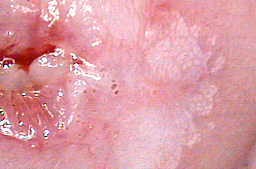

Vagina lesiones por vph planas y acuminadas

Vulva lesiones planas, micropapilares y acuminadas

ECTROPION DE GRAN EXTENSION, tratado mediante fotovaporización con láser CO2

Cicatrización al mes del tratamiento y cicatrización al sexto mes del tratamiento